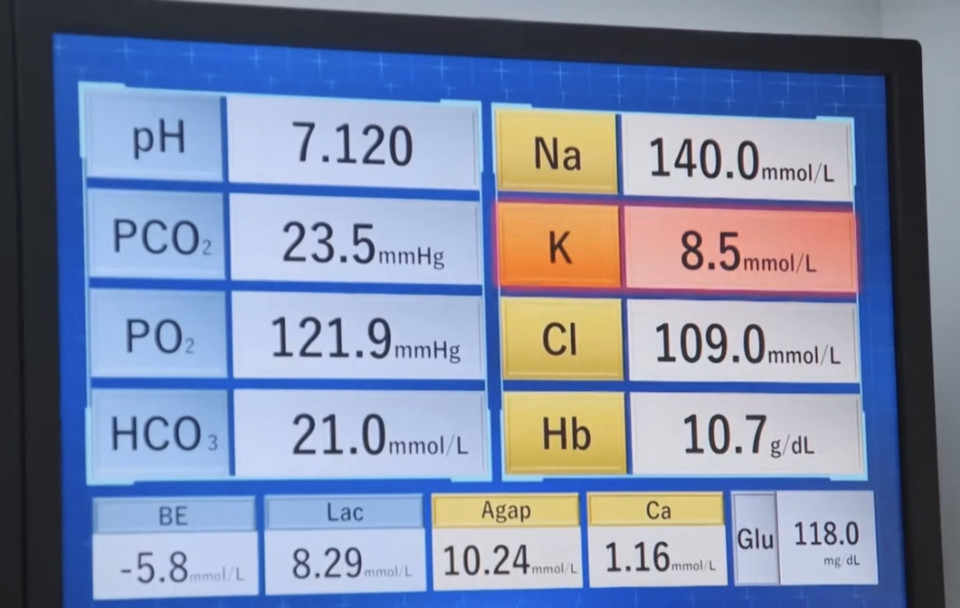

少女の母親より、Ⅰ型糖尿病であることが告げられています

糖尿病とは

インスリン分泌障害および様々な程度の末梢インスリン抵抗性であり,高血糖をもたらします。

食前に上記のインスリンを投与したが、食事摂取をしていないため低血糖発作を起こしている

血糖測定(値は不明)

50%ブドウ糖注射液を静脈注射